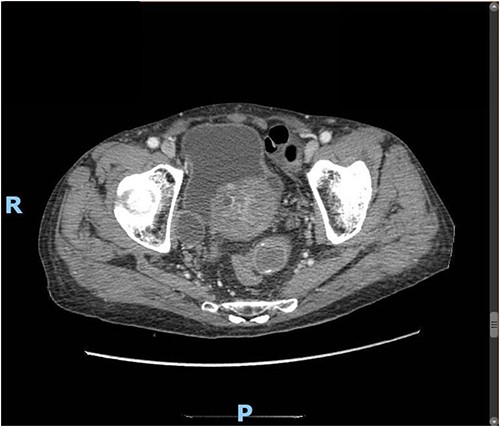

Upon clinical examination, the patient was vitally stable. Abdominal examination revealed a distended abdomen with generalized tenderness. Digital rectal examination revealed an empty rectum with no palpable masses. Laboratory investigations were unremarkable (Table 1). Abdominal X-ray was done (Fig. 2) and showed dilated large bowel loops suggestive of bowel obstruction. Enhanced CT scan of the abdomen and pelvis was obtained (Figs 3–5) and showed a dilated large bowel loop, with air fluid level. A 2.5-cm gallstone was noted, impacting the sigmoid colon and causing partial large bowel obstruction. There was evidence of pneumobilia with air foci within the gallbladder with a suspected fistula with the hepatic flexure.

Enhanced CT scan of the abdomen showing a gallbladder stone impacted at the sigmoid colon, with a significantly enlarged prostate causing narrowing of the rectosigmoid junction (axial view).